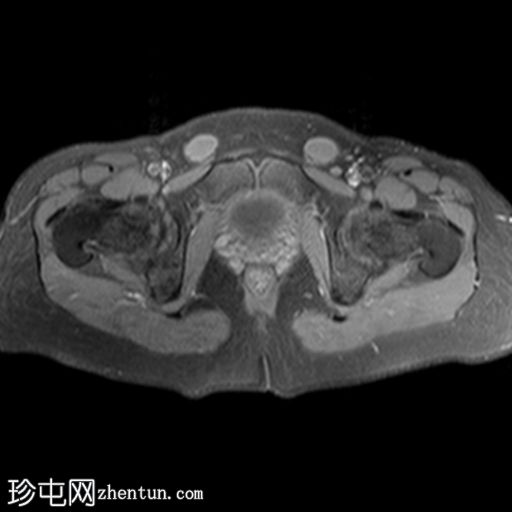

轴位

T1加权像

子宫缺失

卵巢缺失

阴道下三分之一发育不全,上三分之二缺失

可见双侧腹股沟卵圆形结构,提示隐睾(右侧约2.4×2厘米,左侧约2.3×2厘米)

上述特征符合雄激素不敏感综合征(睾丸女性化综合征)的典型表现。

核型分析显示46XY染色体。